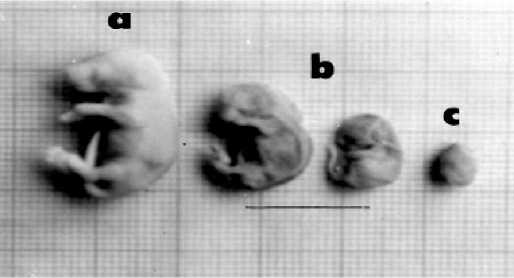

signifikan (p < 0,05) baru mulai dosis perlakuan 15 g/g bb/hari. Fetus mengalami resorbsi pada pemberian dosis 7,5; 15 dan 22,5 g/g bb/hari. Rerata jumlah fetus yang mengalami resorbsi meningkat dengan meningkatnya dosis ekstrak yang diberikan (Tabel 1). Morfologi fetus normal, fetus kerdil dan fetus yang mengalami resorpsi ditampilkan pada Gambar 1.

Gambar 1. Morfologi fetus mencit (a). Fetus normal, (b). Fetus kerdil dari kelompok dosis 22,5 g/g bb/hari, (c). Fetus resorbsi dari dosis 22,5 g/g bb/hari

Rerata berat fetus cenderung menurun dengan meningkatnya dosis. Rerata berat di bawah normal tampak pada dosis 15 dan 22,5 g/g bb/hari (Tabel 2). Morfologi fetus dengan kelainan berat dan panjang juga dapat dilihat pada Gambar 1.